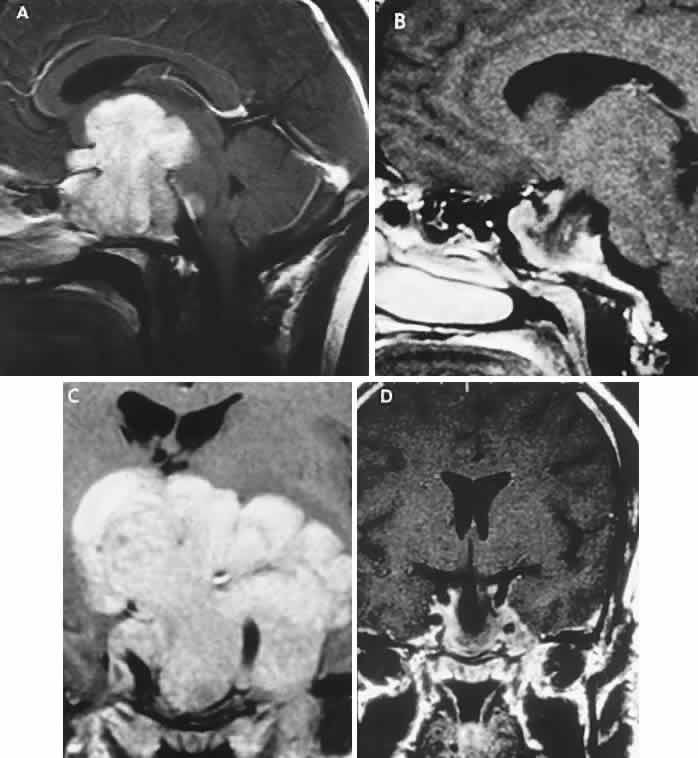

The absence of field defects, for example, in patients undergoing evaluation for amenorrhea, galactorrhea, or sellar enlargement incidentally discovered, does not imply the absence of an adenoma. Obviously, patients with microadenomas, that is, confined within the sella, do not have field defects. From a study24 of 50 cases of pituitary adenomas with chiasmal syndrome, it was concluded that visual disturbance occurs when the chiasm is displaced approximately 10 mm upward (see also Volume 2, Chapter 4, Fig. 6). The modern management of pituitary adenomas should involve several disciplines: current neuroradiologic studies detect microadenomas and provide precise delineation of gross morphology and status of neighboring structures, and mixed MRI signals suggest new or old hemorrhage, cysts, and so forth (Fig. 2); radioimmunoassay techniques assay PRL and other endocrine levels; oral neuropharmacologic agents, such as bromergocryptine, provide a “medical adenomectomy” for hyperprolactinemia and acromegaly; transsphenoidal surgery, including high-illumination microscopical procedures, televised radiofluoroscopic monitoring, and infection control, has all but replaced transcranial approaches; immunohistochemistry techniques have replaced the anachronistic tinctorial designations (e.g., chromophobe, basophilic) with a functional classification.

Fig. 2. Large prolactinoma. Original vision in the right eye (RE) was 8/200, left eye (LE) 1/200, with serum prolactin of 26,000 ng/ml and galactorrhea. Four months of bromocriptine reduced prolactin to 661 ng/ml, vision improved to RE 20/40, LE 20/50. At 3 years, vision was as follows: RE 20/30, LE 20/20; prolactin was 25.9 ng/ml. Enhanced magnetic resonance imaging. Sagittal (A) and coronal (C) images at diagnosis. Sagittal (B) and coronal (D) images at 2-year follow-up, showing dramatic shrinkage of the mass.